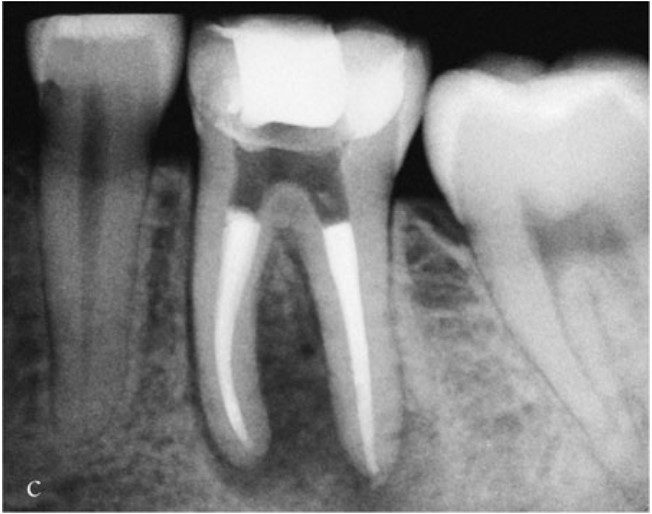

Thực tế thì hiếm khi xoang mở tủy có hình dạng hoàn toàn giống mô tả điển hình trong sách giáo khoa — tức là hình dạng của răng trẻ, chưa từng được phục hồi.

Trên thực tế thì kích thước buồng tủy và vị trí miệng ống tủy bị ảnh hưởng bởi lượng và vị trí ngà thứ cấp, ngà bậc ba được bồi đắp để đáp ứng với sâu răng, phục hồi, rò rỉ hoặc mòn răng theo thời gian.

Những tác động tích lũy này có thể làm thay đổi đáng kể kích thước và hình dạng buồng tủy.

Vật liệu trám bít ống tủy cần kết thúc ở chóp răng tại điểm giới hạn của quá trình tạo hình (điểm thắt chóp). Ở phía thân răng, vật liệu trám bít nên dừng lại cách miệng ống tủy từ 1–2 mm. Trong những trường hợp có tiêu xương nha chu thì phần trám bít nên dừng lại cách mào xương ổ 1–2 mm, nhằm tránh việc vật liệu trám bị lộ ra môi trường miệng qua các ống ngà còn thông.

Nếu có kế hoạch thực hiện phục hình có chốt lưu giữ thì ống chốt nên được sửa soạn ngay sau khi hoàn tất trám bít ống tủy.